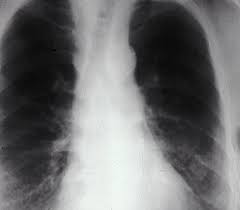

Asbestosis is a respiratory disease caused by inhaling asbestos fibers, in which the lungs extensive scar tissue is formed.

Asbestosis is a respiratory disease caused by exposure to and inhaling asbestos fibers.

Asbestosis is also called idiopathic interstitial pneumonitis, asbestosis affects the lung parenchymal tissue, and is characterized by symptoms such as dyspnea, or shortness of breath, and increased risk of developing various types of lung cancer. In fact, mesothelioma is a complication that can arise in patients with asbestosis.

While mesothelioma and asbestosis are often considered mutually define the terms the same cancer, it is important to note that asbestosis and mesothelioma are very different diseases. Mesothelioma is a malignant form of cancer that affects the mesothelial lining in the body. Asbestosis, on the other hand, is a non-cancerous scarring of lung tissue.

The main symptom of asbestosis is a gradual onset of dyspnea with physical activity. When asbestos fibers are inhaled and reach the air sacs in the lungs where oxygen is transferred into the blood, or alveoli, asbestos particles cause the immune system? to try to expel fibers by producing an inflammatory response. As the body attempts to expel foreign particles, forming a fibrous mass resulting in interstitial fibrosis. As the fibrotic scar tissue thickens the walls of the alveoli, the lungs lose their ability to function and remove carbon dioxide. As the disease advances, respiratory failure can occur as the disease causes the lungs lose their elasticity and ability to expand and contract. Also in very severe cases of asbestosis reduced total lung capacity and lungs become stiff, eventually causing heart failure. More than 50% of patients affected with asbestosis develop plaques in the space between the chest wall and lungs, and patients can also see clubbing fingers as asbestosis worsens. Coughing is not usually associated with asbestosis, but may show other serious respiratory illnesses.